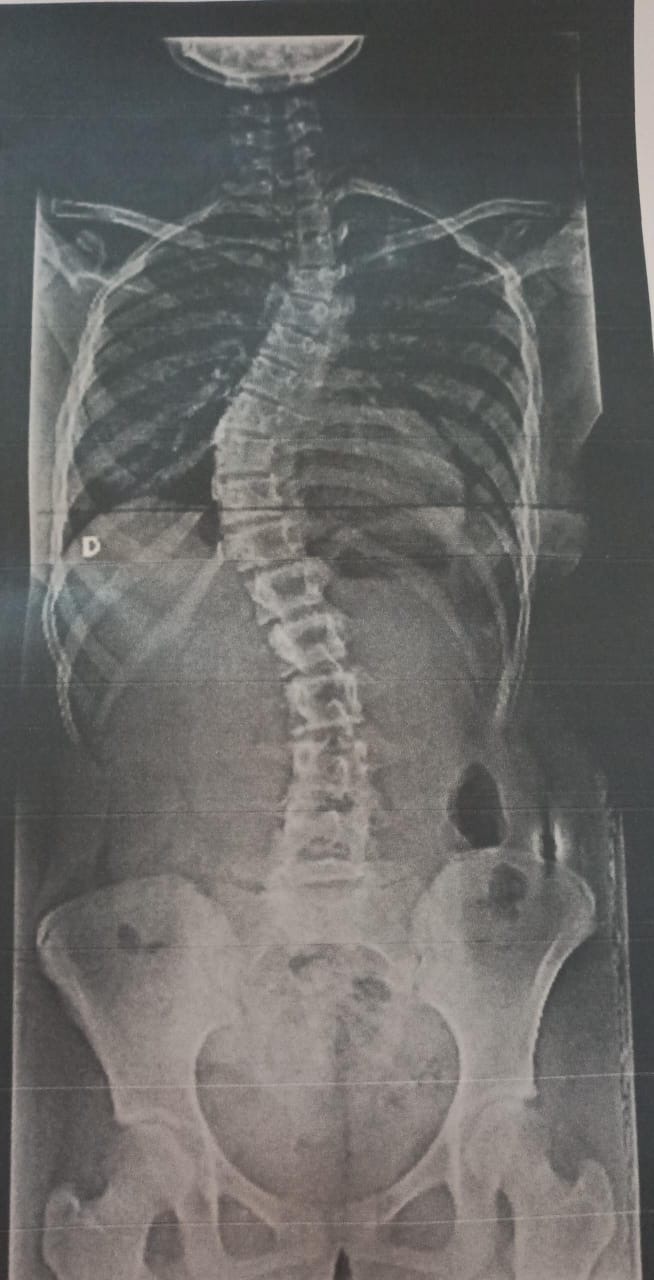

Hoy me atrevo a compartir esto porque realmente necesito ayuda, tengo 15 años y fui diagnosticada con Escoliosis Idiopática del Adolescente, una enfermedad que está deformando mi columna y que avanza muy rápido.

Desde hace un tiempo he estado sufriendo fuertes dolores de espalda, y los médicos indicaron que necesito una operación de columna con urgencia, ya que si no se realiza a tiempo puede causar complicaciones respiratorias graves